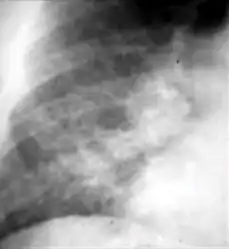

Chest x-ray showing coarse reticulonodular densities on the lower right lung of post-primary pulmonary TB.